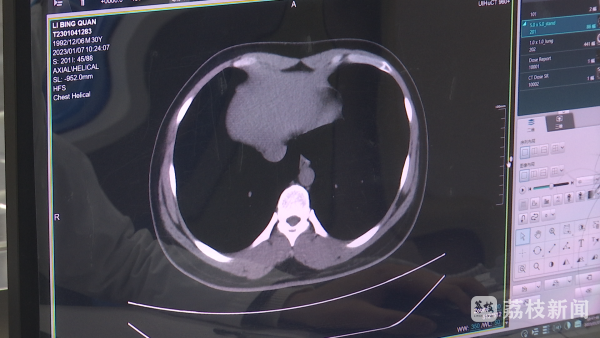

江苏省第二中医院的健康管理中心主任金黑鹰告诉记者:“主要是针对新冠阳性以后,主要损害的靶器官,肺、心脏、肝脏和肾,做肺部CT看一下会不会有残余的炎症。有些人比如说长期咳嗽的,还是有一些肺部炎症表现,当然这些炎症比较轻,一般来讲没有太大的问题。另外在心脏方面,可能有的人会出现心肌炎的表现。”

南京鼓楼医院江北院区健康管理中心主任申志祥:“因为很多的症状和体征跟影像学是不同步的,有的人感觉挺好的,但是实际上肺里面炎症还没有消退,或者是恢复很慢。老年人我们认为是值得要重视的,因为他本身的活动量少,不会出现像年轻人活动量多以后,心慌气短,他就感觉不舒服,但是这些人往往一旦出现沉默性缺氧,进展是比较快的、预后是比较差的。”